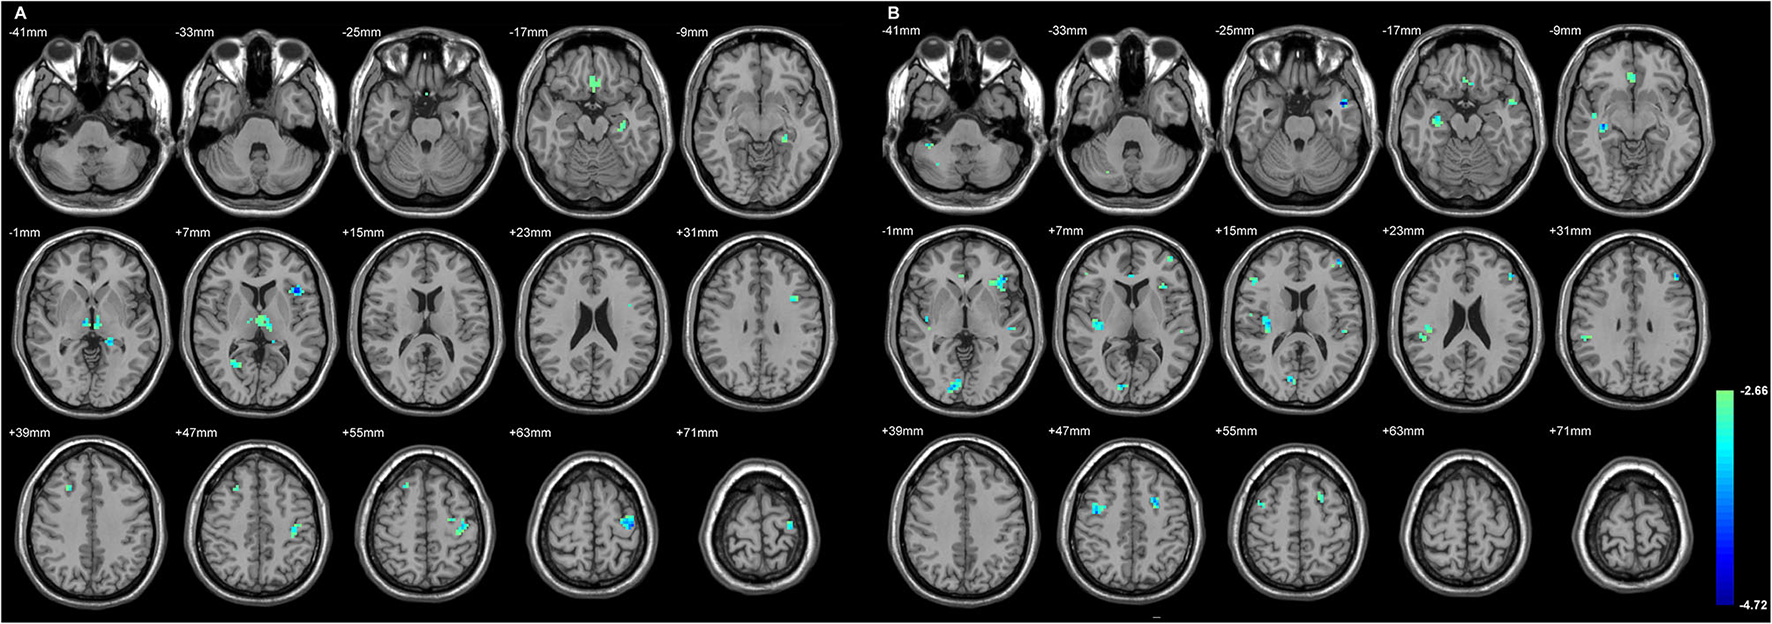

The Extratemporal GMD Decreased in Both TLE, Primarily Involving Parts of the Frontal Lobe

Figure 2 and Table 4 showed the significant GMD changes in both TLE groups compared with the controls. The commonly affected regions were the ipsilateral inferior frontal gyrus, precentral gyrus, and medial orbital cortex. Moreover, both TLE groups had significant GMD decreases over the left middle frontal gyrus and around the right calcarine areas. The cortex and its associations of GMD with epilepsy duration are listed in Table 5 and Figure 3.

Figure 2

The cortices with significant gray matter density (GMD) changes compared with the normal controls, using age and gender as the covariates (A) in L-TLE, and (B) in right-LTE (R-TLE). All involved regions in both TLE showed decreased GMD, mostly located in the frontal and temporal lobes. Ipsilateral inferior frontal gyrus, precentral gyrus, and medial orbital cortices were affected in both TLE. A T-test comparison was performed between the two groups, using a double statistical threshold (height threshold p < 0.01 and a minimum cluster size = 354 voxels, as determined by the AlphaSim correction).

Figure 3

The regions with their GMD related to the epilepsy duration. The longer duration was related to decreased GMD in both TLE. (A) The involved cortices in L-TLE were in the left temporal and right inferior frontal areas. (B) The involved cortices in R-TLE were in the right temporal and left cerebellar areas. Differences with a p < 0.01 were considered significant (with a threshold p < 0.01 and a minimum cluster size = 354 voxels, as determined by the AlphaSim correction).